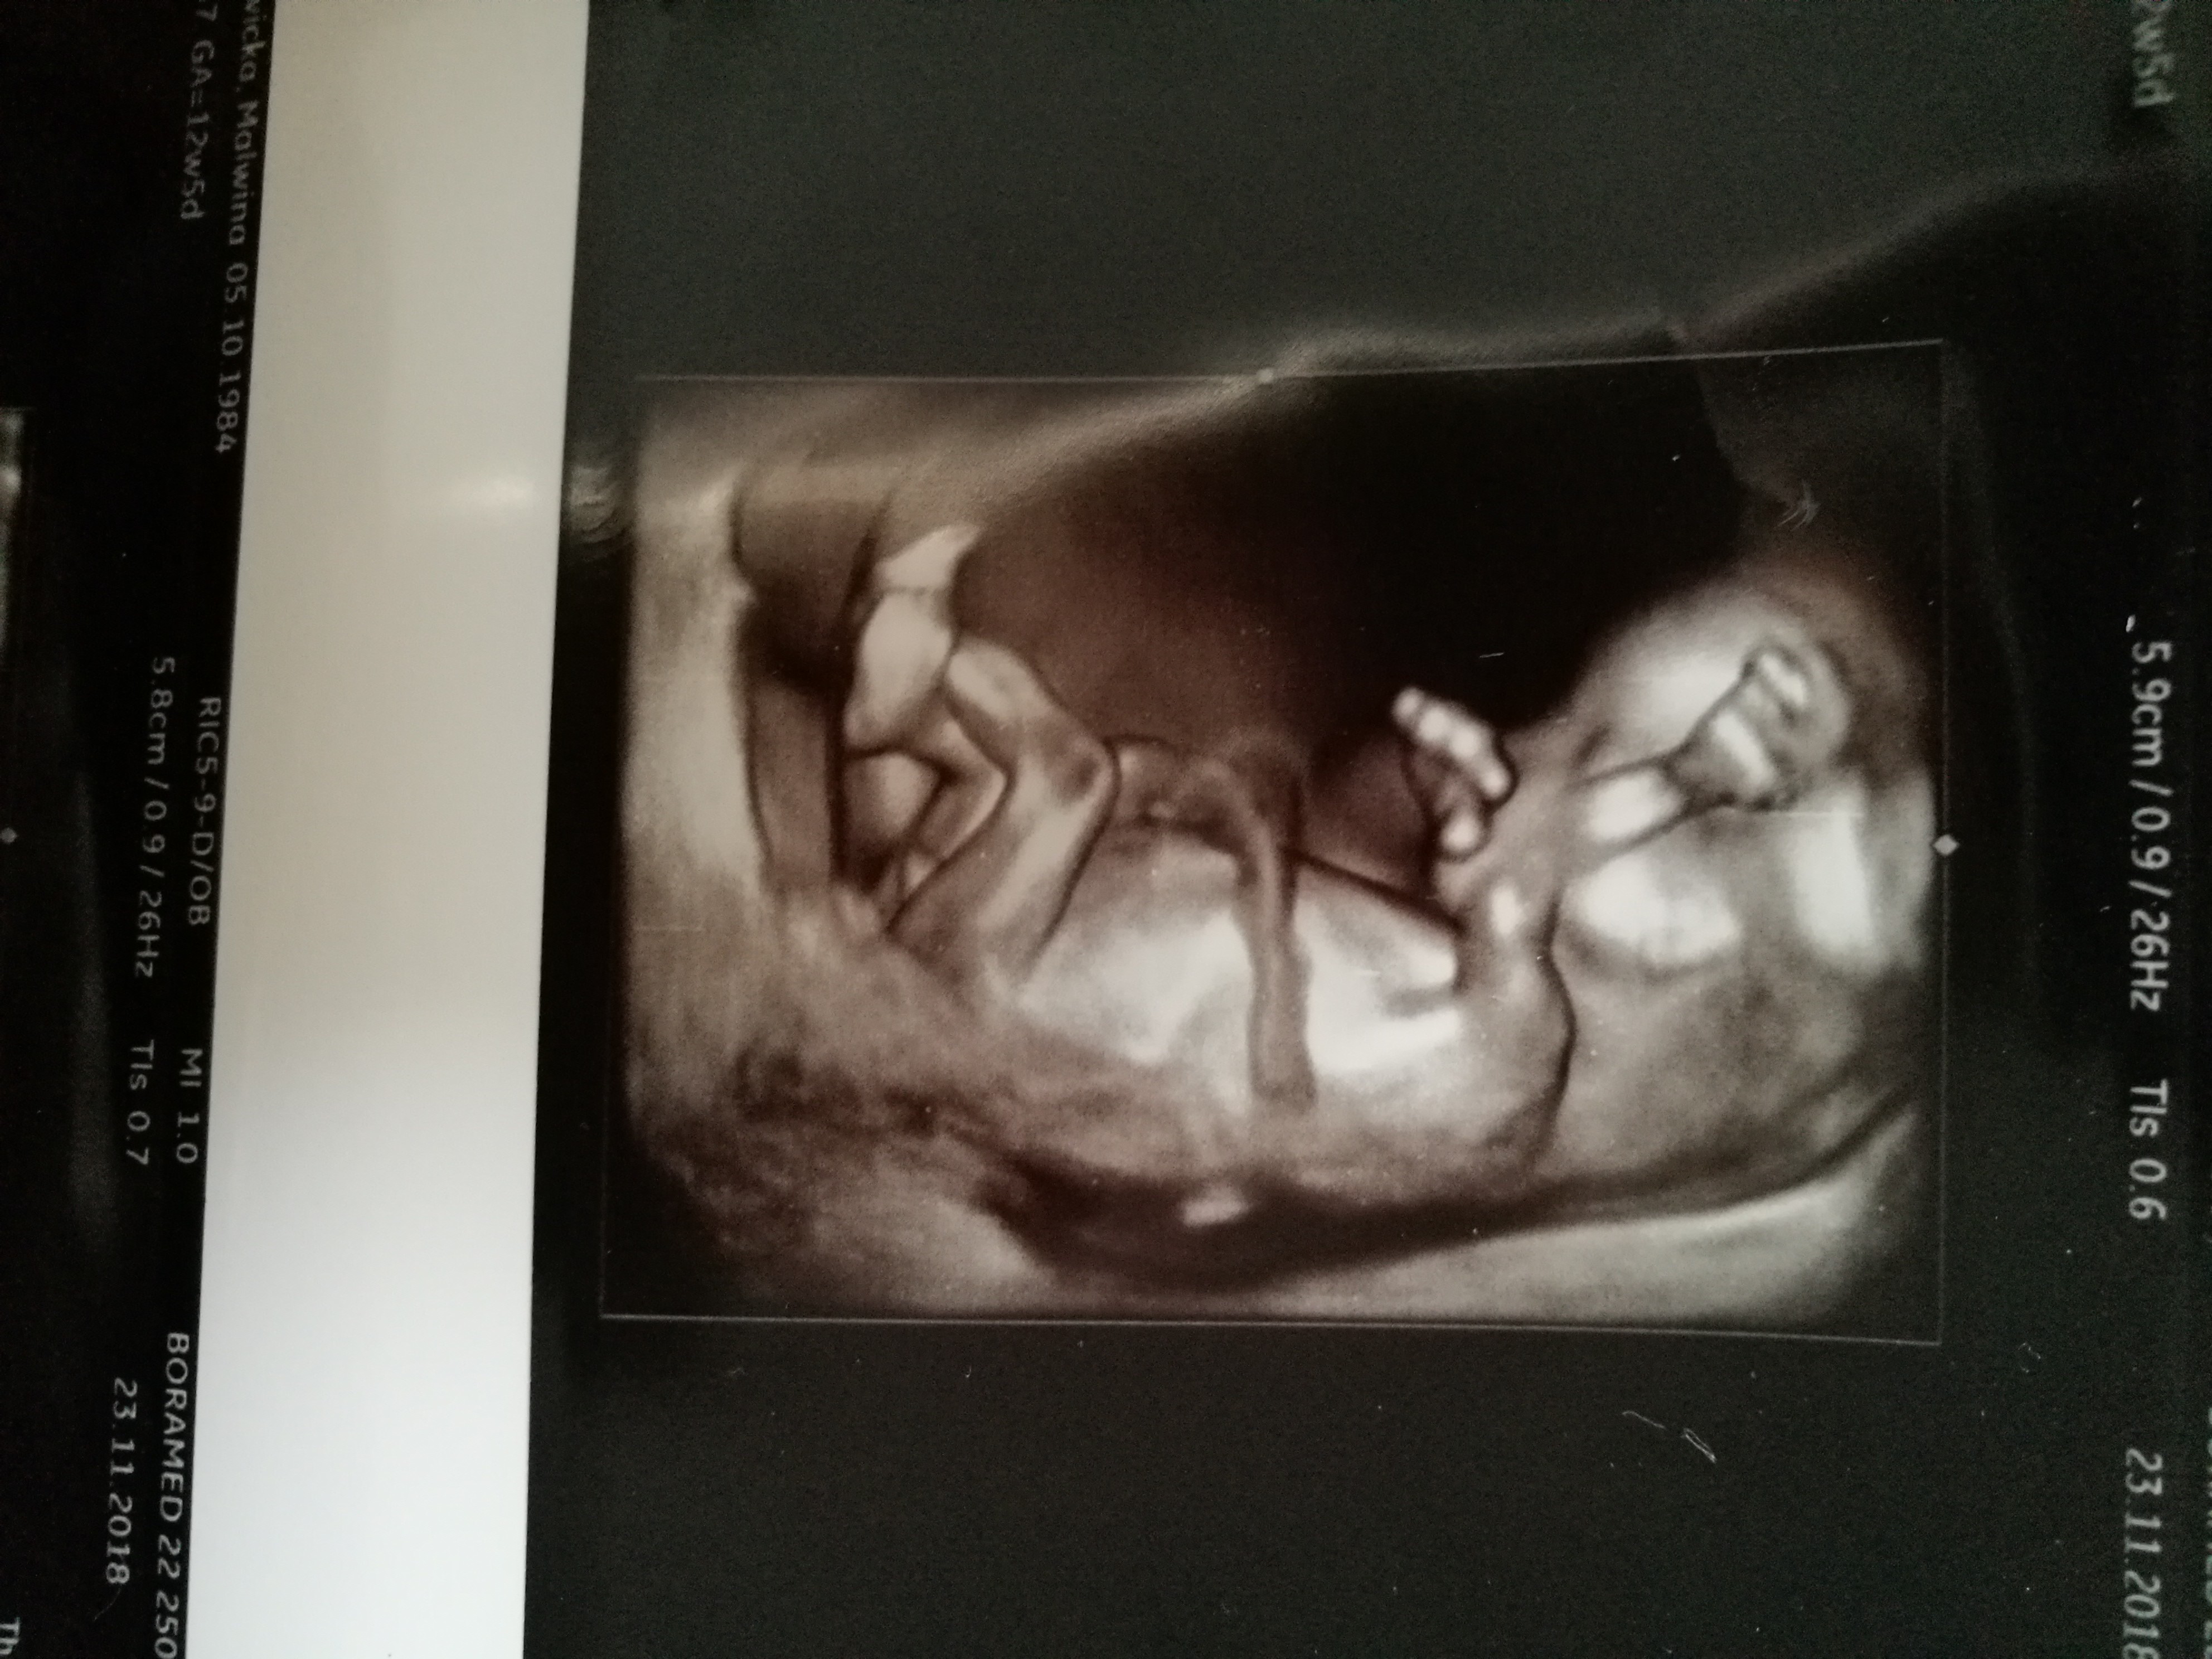

Cześć dziewczyny. Co sądzicie o moich zdjęciach? W 11tc5dc pierwsze zdj-lekarz stwierdził że na 75prc. dziewczynka. Tydzien później jeszcze raz byłam u niego, bo jeszcze musiał coś podejrzeć i w 12tc5d następne zdjęcia-powiedział że dziś na 75 prc. chłopak. Powiedział ogólnie że daje 50proc i trzeba poczekać do połówkowego. Czy ktoś miał tak szybką zmianę płci. Zdjęcia z obydwu badań wydają się jednoznaczne: na pierwszym dziewczynka, na drugim chłopiec. Czy już zostanie chłopiec?? Czy jest szansa że się zmieni? Ktoś tak miał? Dałybyście 100proc chłopak, czy jakąś nadzieję na dziewczynkę? Lekarz uznał, że jest jakiś procent kobiet u których się to zmienia, nie wiem co miał na myśli.

Za wczesnie lekarz ocenil plec pierwszym razem dlatego ze nub do 13 tc moze sie podniesc ...na poczatku wszystkie nuby sa dziewczynkowe.Raczej nastawialbym sie na chlopca ale poczekaj na polowkowe.